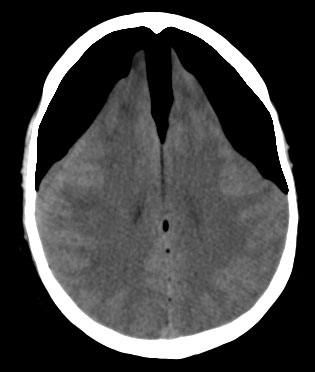

SIGNO DEL CEREBELO BLANCO o SIGNO INVERSO

Las imágenes muestran el cerebelo blanco. Se trataba de una niña que sufrió ahogamiento en una piscina.

Es un signo de edema cerebral difuso en la TC, también llamado signo del cerebelo denso o signo inverso (reversal sign). El cerebro muestra una disminución difusa de la densidad y una pérdida de la diferenciación entre la sustancia gris y la sustancia blanca, mientras que, el cerebelo -en cambio- está relativamente hiperdenso con respecto a los hemisferios cerebrales. También quedan respetados los tálamos y el tronco cerebral.

Este signo se ha descrito en cuadros de daño cerebral hipóxico como asfixia neonatal, ahogamiento, status epiléptico, meningitis bacteriana y encefalitis. Indica un daño cerebral irreversible con pésimo pronóstico.

No se conoce con exactitud la fisiopatología pero se postula que se produce por redistribución del flujo inracraneal con preservación de la circulación posterior y edema cerebral secundario.

La imagen corresponde a una niña que sufrió un ahogamiento en una piscina.